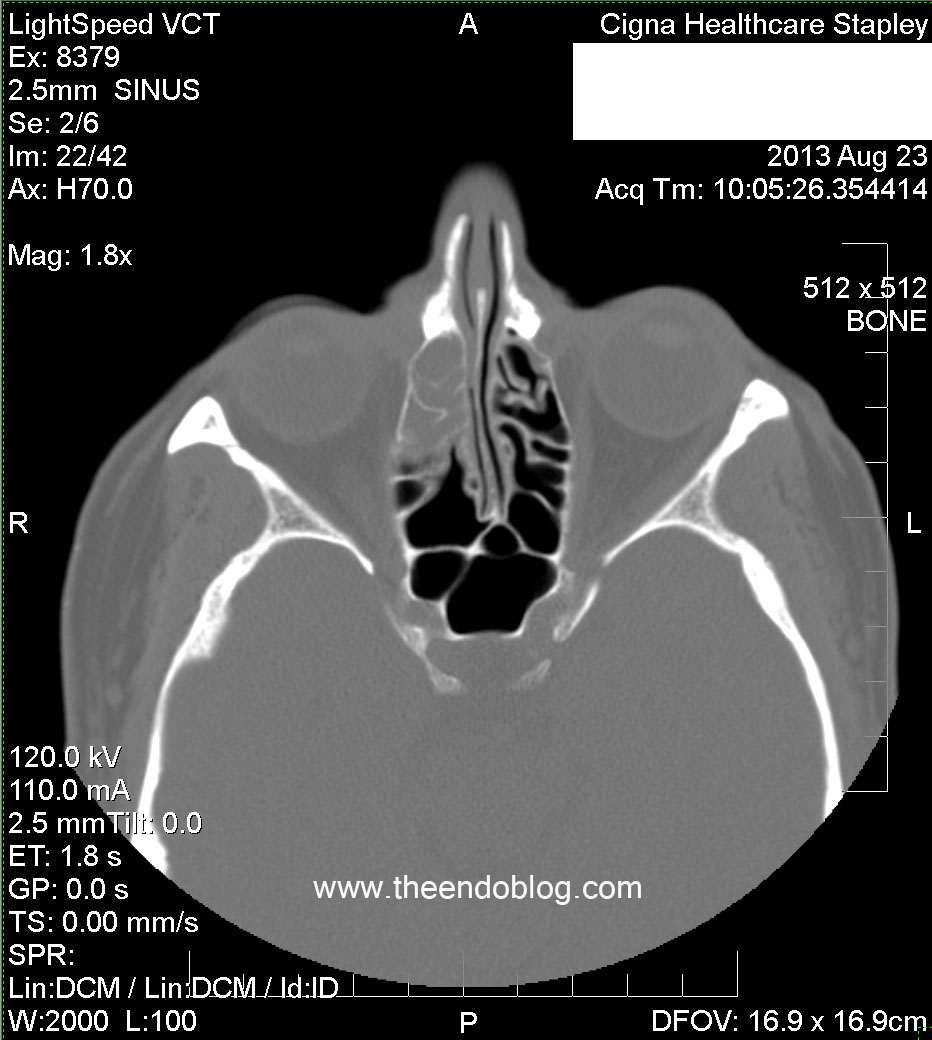

RADIOGRAPHIC FINDINGS:

Complete opacification of the right frontal sinus.

Partial opacification of the R ethmoid sinuses.

Complete opacification of R maxilliary sinus, superior septal deviation to the right, bilateral opacified concha bullosas.

Molar #2 and #3 have periapical radiolucency (PARL), one of which is dehiscent into the maxillary sinus and buccal gingival sulcus.  This may be the most important diagnostic information in the CT scan.  Too often, radiologists and otolaryngologists are not looking at this part of the scan - if it is even included in the field of view.